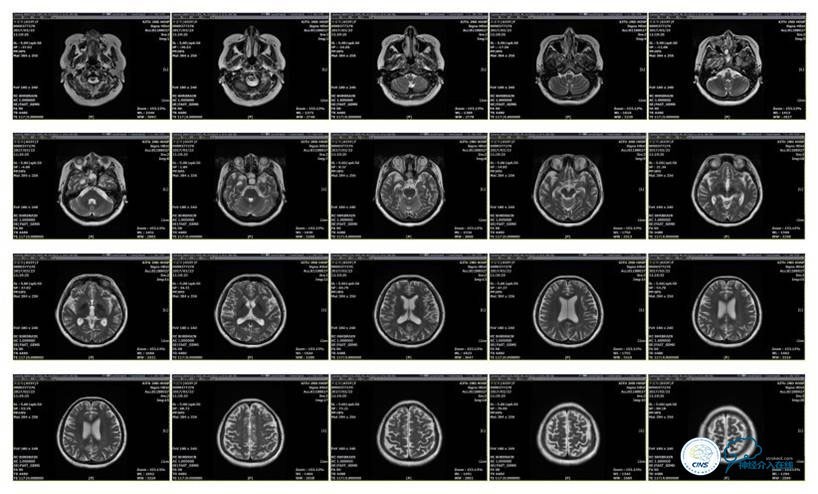

2016-5-19 MRI

2016-05-20 MRV

2016-06-03 CT

2017-06-07 CT

病史:患者于1年余前,因人流术后出现发作性四肢抽搐伴口吐白沫,头痛及双眼视力下降在外院行颅脑MRI及MRV提示:右侧横窦、乙状窦狭窄,予以低分子肝素抗凝治疗2周,颅内压无明显下降,视力下降严重,遂行脑室腹腔分流术,术后患者头痛缓解、双眼视力稍有改善。2周前患者再次出现头痛、发作性四肢抽搐及视力下降,在外院眼科予以治疗2周,头痛无明显改善,视力再次逐渐下降,遂转入我科。

诊断:1、右侧横窦、乙状窦狭窄;2、继发性癫痫;3、双侧视神经萎缩;4、脑室腹腔分流术后;5、椎管内占位切除术后。

诊疗方案:为挽救视力,确定支架成形术效果,急诊行右侧横窦乙状窦狭窄球囊扩张术(6mm×20mm,Ever Cross )。